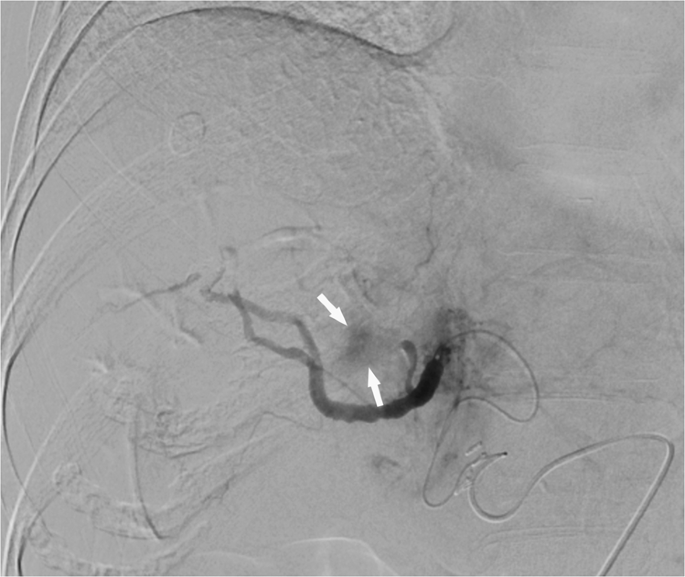

The periprocedural angiographic images were interpreted by two independent diagnostic radiologists using the same imaging protocol as the baseline. To standardize the measurements, definition and quantitative measurement for each parameter were discussed before image interpretation to reach consensus. The individual image reviews by both readers were used to calculate interobserver variability. The definitions of baseline CT or MR images were reviewed as follows: (1) Arterial-phase hyperenhancement. (2) Washout in portal-venous phase or delayed phase. (3) Enhancing capsule, defined as an enhanced, sharp border surrounding the mass that persisted in the portal-venous phase or delayed phase. (4) Tumor morphology: classified as ill-defined or well-defined margins. (5) Cystic necrosis or degeneration, defined as present if larger than 50% of the tumor volume. (6) Macroscopic vessel involvement, defined as direct invasion or thrombus of the portal vein, hepatic vein, or inferior vena cava detected macroscopically. (7) Exophytic growth, defined as outward growth beyond the capsule. (8) Intrahepatic vascular shunt: showing peri-tumoral transient hepatic attenuation differences or early portal vein enhancement in the arterial phase before enhancement of the main portal branches. Perioperative angiographic findings were evaluated with the following definitions: (1) Largest feeding artery diameter was measured at the entry site of each vessel into each target lesion and compared to the inner diameter of the microcatheter on a case-by-case basis. (2) Number of tumor-supplying first-order branches of the celiac trunk, superior mesenteric artery and in some cases, directly from abdominal aorta. (3) Vascular lake phenomenon (VLP), defined as localized intra-tumoral contrast accumulation during angiography when injecting microspheres into the tumor. (Fig. 2) (4) Homogeneous tumor enhancement (HTE), defined as uniform contrast distribution without missing any corner of the target lesion during the arterial-phase scan of superselective, preprocedural cone-beam CT (CBCT) (Fig. 3). (5) Residual tumor blush, which presents as residual intra-tumoral enhancement on completion arteriography during TACE (Fig. 4).

Right hepatic angiogram shows a (a) vascular lake that presents as localized contrast pooling (white arrow) during angiography. (b) Superselective angiogram shows disappearance of the vascular lakes, and no contrast extravasation was observed.